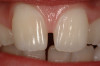

Figure 15. Fiber-reinforced composite bridge placed 7 years prior in the hope of patient having an implant placed in the left central position.

Figure 15